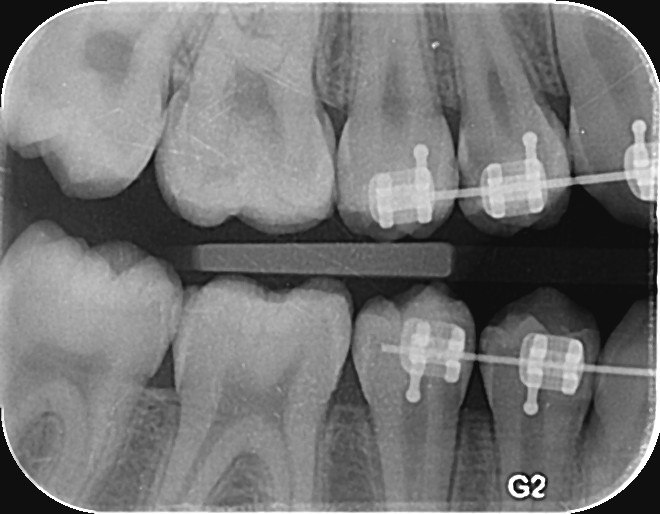

4. What surface require restoration?